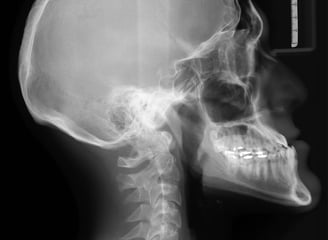

Digital X-Rays

On site X-rays assist in accessing your condition to treat you more effectively and also rule out conditions you may have if you need to be referred to another physician.